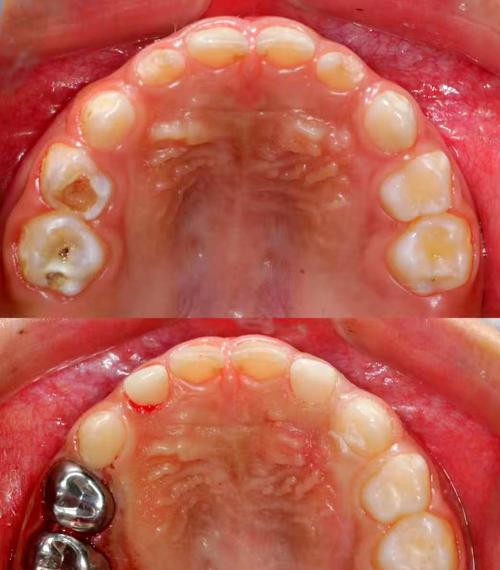

美容冠主要针对牙齿形态、色泽或轻微排列异常的改善,通过将牙齿磨小后制作全瓷冠或烤瓷冠,覆盖于原牙表面,快速实现“美牙”效果,其核心优势是治疗周期短(通常7-14天),能同时解决牙齿颜色、形状、大小等问题,尤其适用于牙齿过小、牙缝过大、氟斑牙、四环素牙等,根据材质不同,美容冠可分为全瓷冠(如氧化锆、e.max,生物相容性好、色泽自然,价格约3000元-8000元/颗)和烤瓷冠(内层金属+外层瓷,价格较低约1500元-4000元/颗,但可能存在金属过敏或牙龈黑线风险)。

矫正牙齿流程包括:初诊检查(口腔检查、X光片、取模)→方案设计→戴矫治器→每月复诊调整→拆除矫治器→佩戴保持器(至少2年),美容冠流程为:初诊检查(口腔评估、比色)→牙齿预备(磨除0.5-1.5mm牙体)→取模(或口扫)→制作临时冠→永久冠试戴(调整咬合、颜色)→粘接→复查。